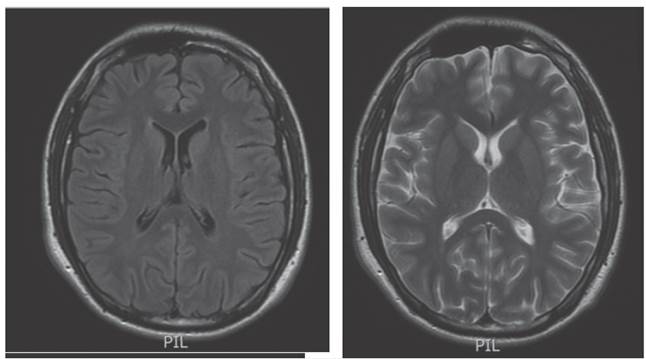

Se hizo nueva resonancia magnética cerebral simple normal (figura 1), se complementó además con tomografía por emisión de positrones normal (figura 2).

Resonancia magnética cerebral simple

Figura 1: Resonancia magnética cerebral simple